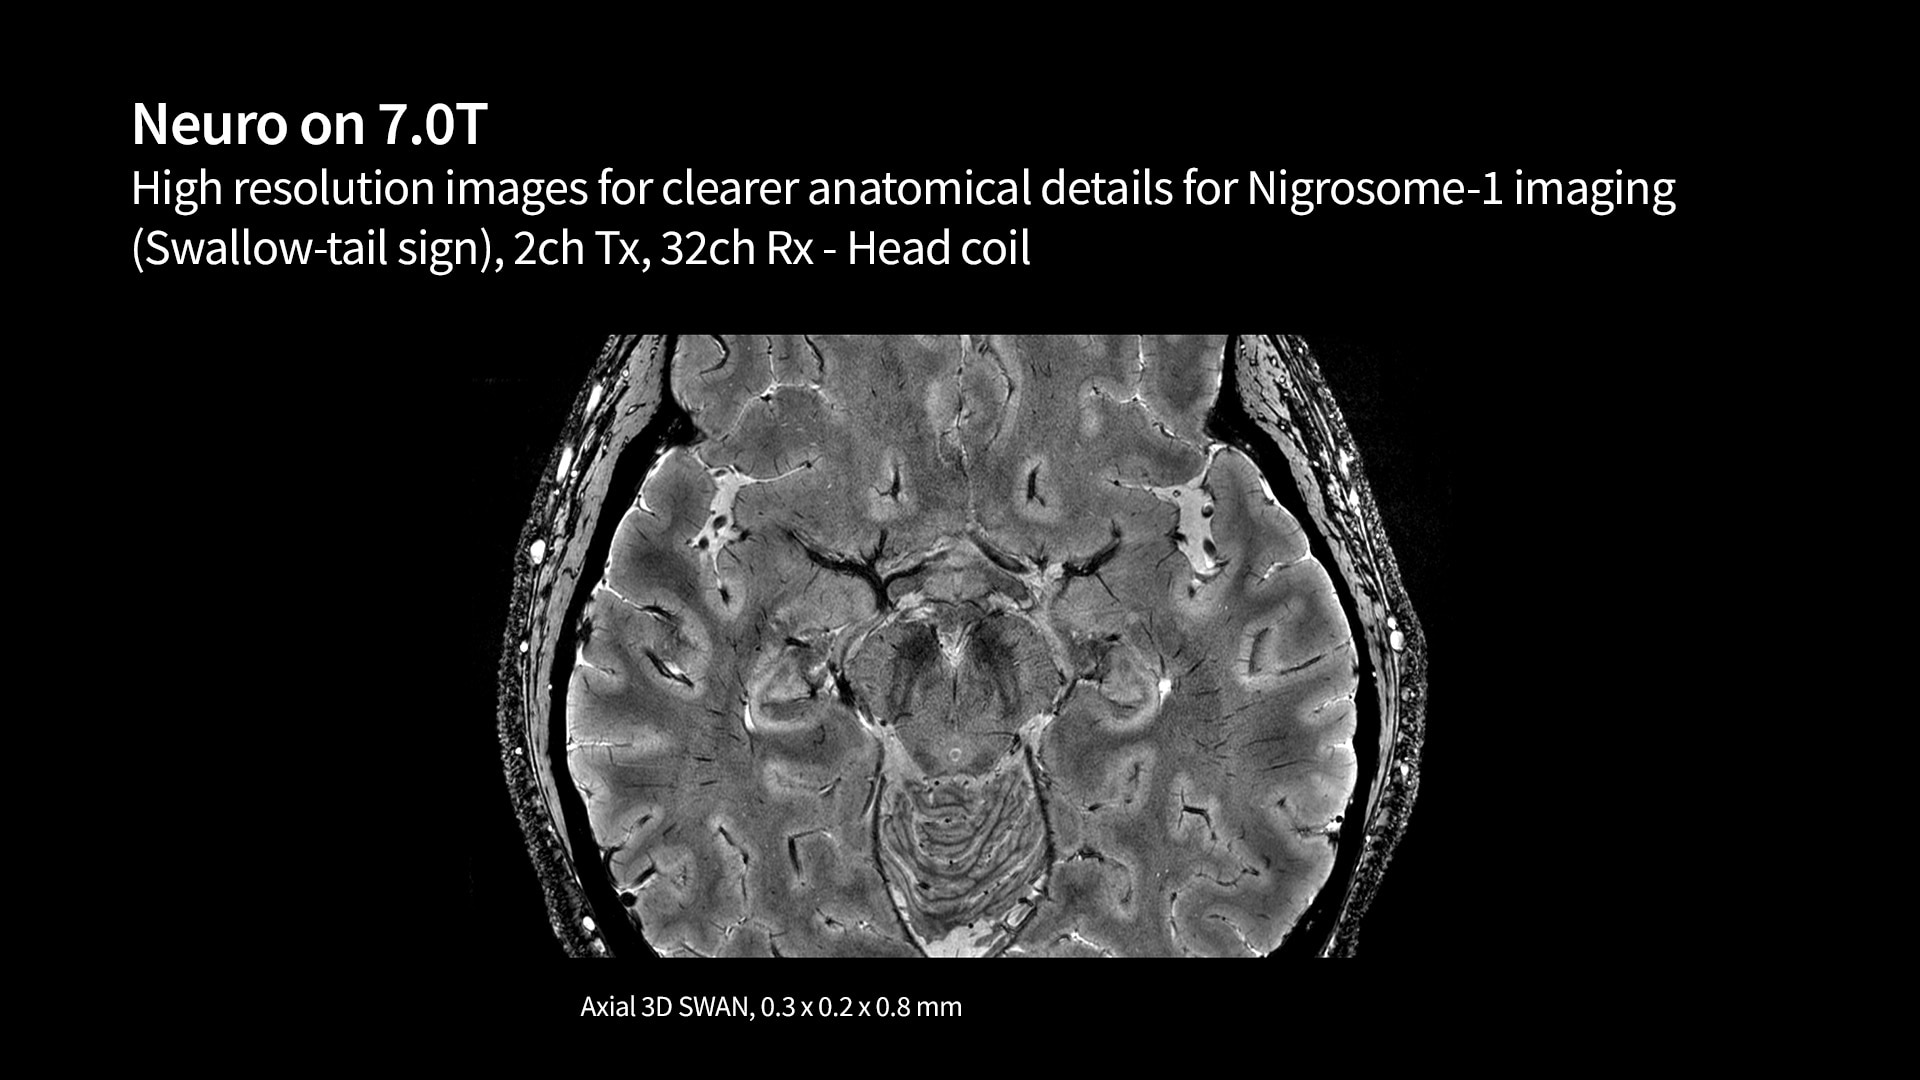

Empowering providers to discover how to fight the most debilitating illnesses

We are helping enable groundbreaking discoveries with a wide array of research-focused MR technology. This technology is opening up research and new care pathways to better understand the world's most debilitating diseases like cancer, as well as neurodegenerative, cardiovascular and psychological diseases. We hope to empower you with ongoing partnerships and continued AI innovation to discover new biomarkers that could lead to significant breakthroughs in your understanding of disease.